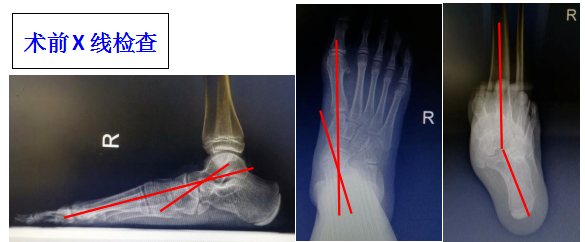

手術前后的影像學改變

【典型案例】左側青少年扁平足,1cm小切口即可解決!